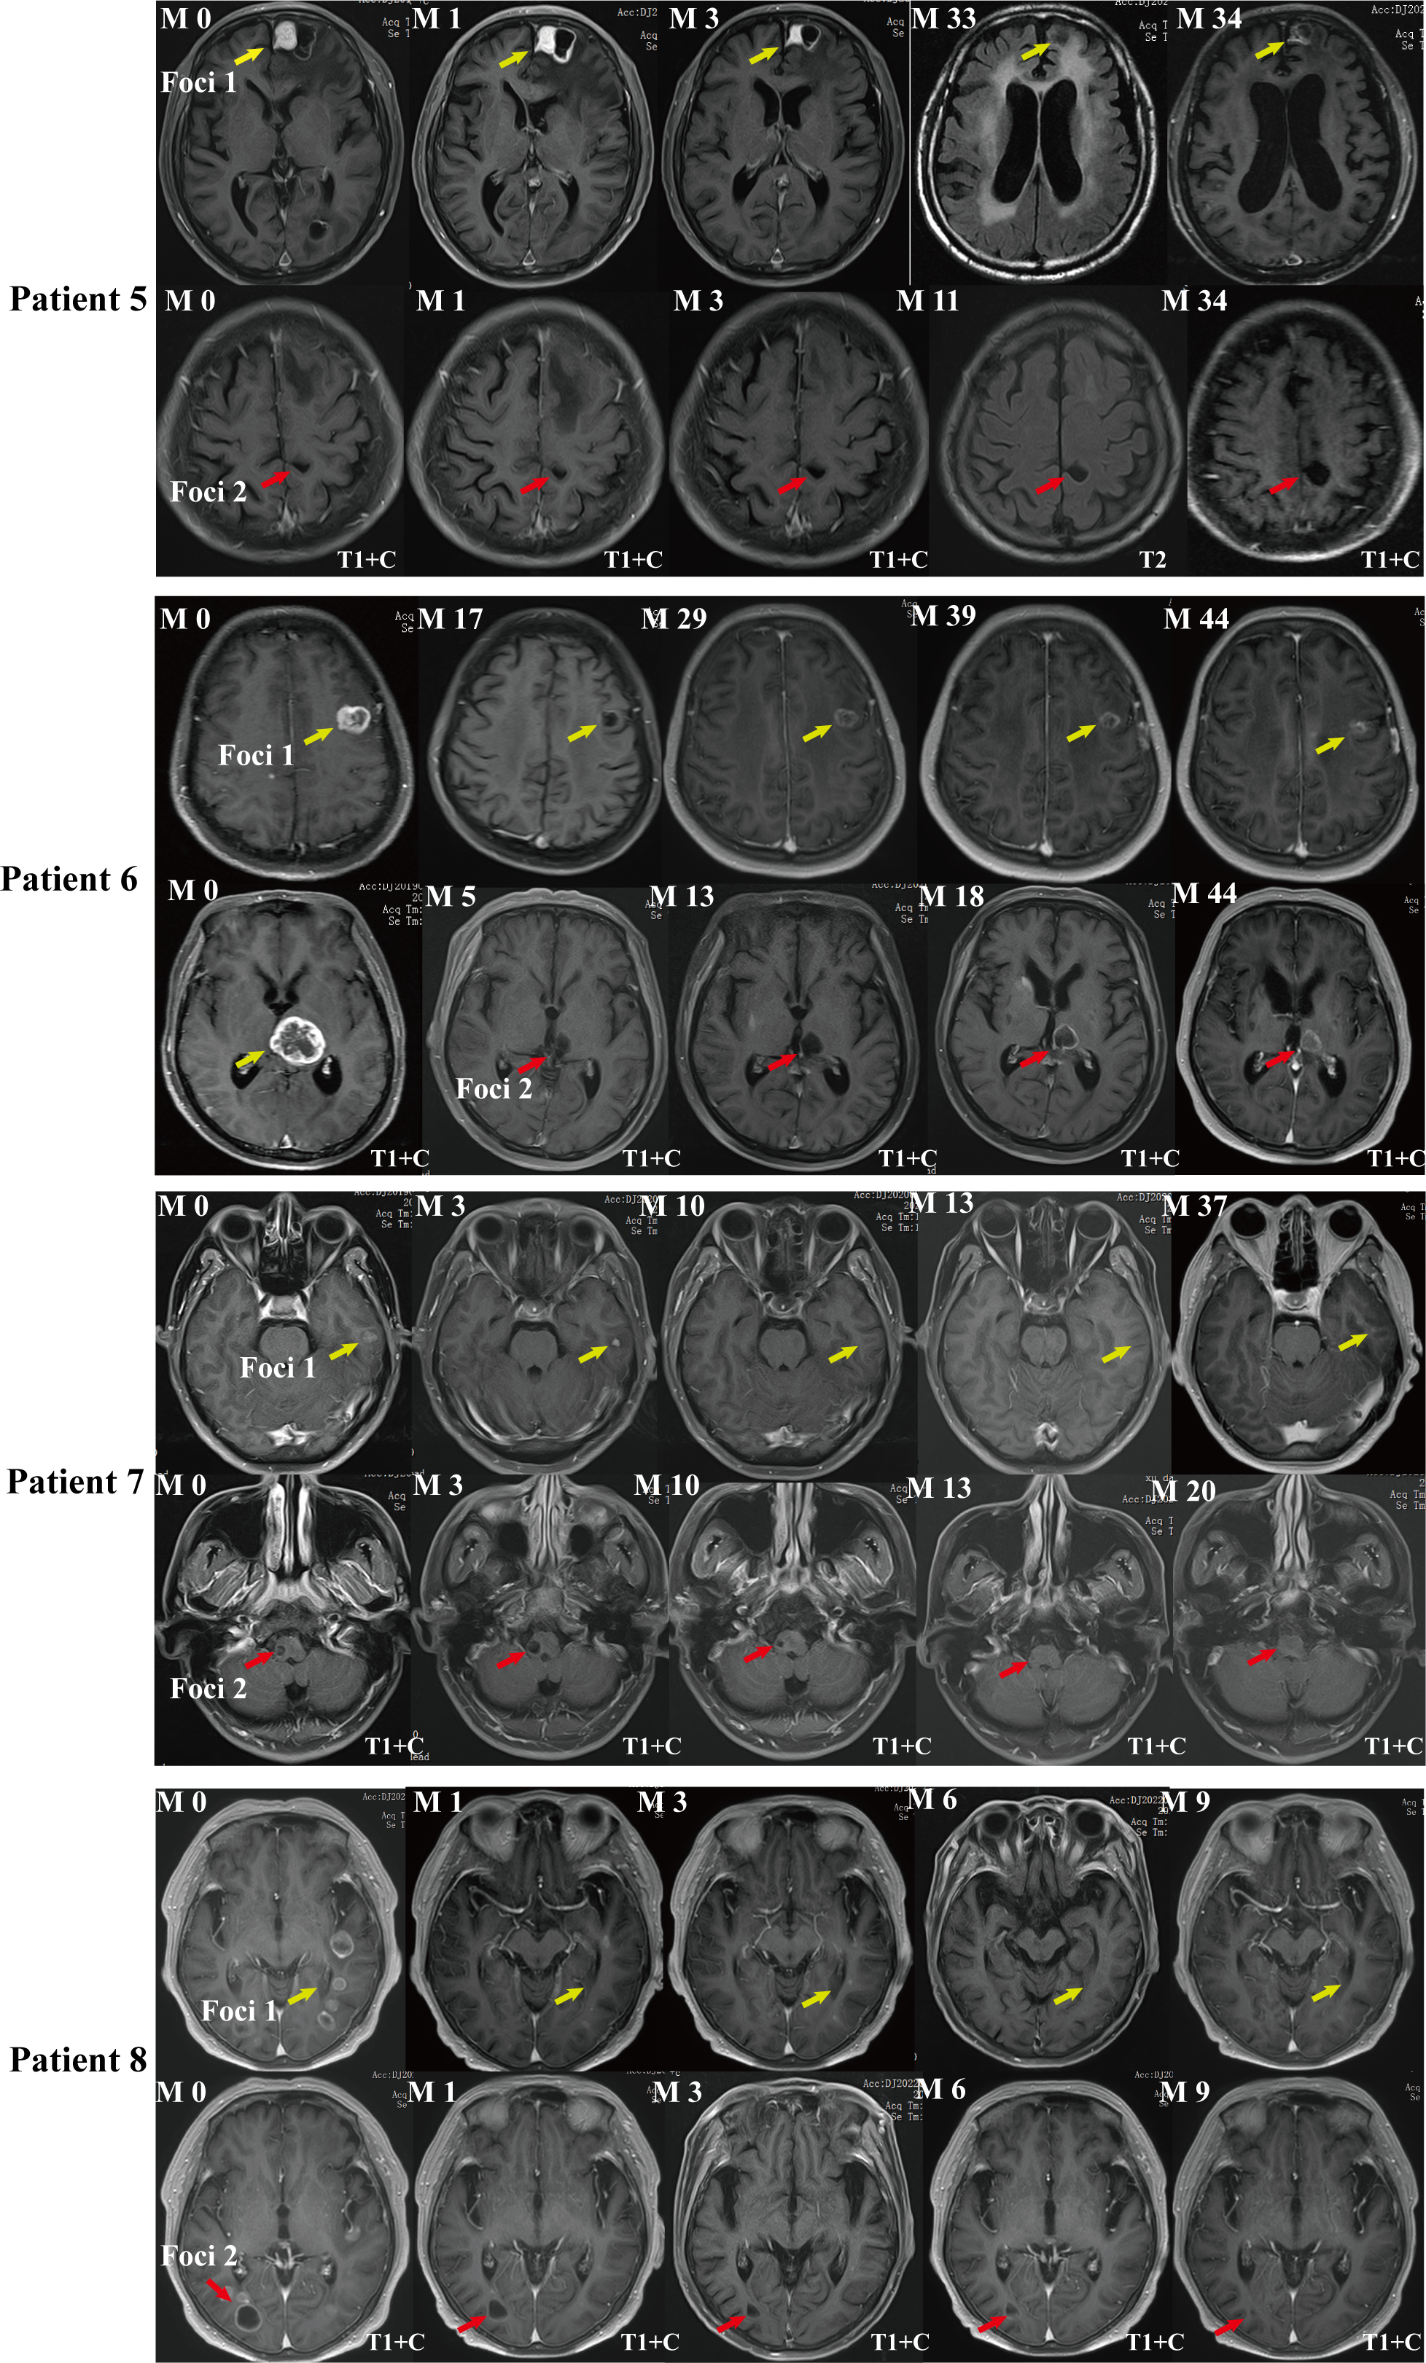

Fig. 2

From: Longitudinal MRI evaluation of the efficacy of non-enhanced lung cancer brain metastases

Comparison of follow-up MR characteristics between non-enhanced and enhanced BM during treatment. Patient 5, Male, 73-year-old, adenocarcinoma of the upper lobe of right lung. The patient was treated with chemotherapy, radiotherapy and targeted therapy according to clinical guidelines. The figure shows axial T2-weighted and T1-weighted enhanced MRI images of left frontal lobe (Foci 1) enhanced and left parietal lobe (Foci 2) non-enhanced metastatic tumors. Patient 6, Female, 54-year-old, adenocarcinoma of the inferior lobe of left lung. The patient was treated with chemotherapy, radiotherapy, targeted therapy and other comprehensive treatment. The figure shows axial enhanced T1-weighted MR images of left frontal lobe (Foci 1) enhanced and left thalamus (Foci 2) non-enhanced metastatic tumors. Patient 7, Male, 33-year-old, adenocarcinoma of the right inferior lung lobe. The patient was treated with chemotherapy, radiotherapy, targeted therapy, immunotherapy and other comprehensive treatment. The figure shows axial enhanced T1-weighted MR images of left temporal lobe (Foci 1) enhanced and brain stem (Foci 2) non-enhanced metastatic tumors. Patient 8, Male, 71-year-old, adenocarcinoma of the inferior lobe of the left lung. He was treated with chemotherapy, radiotherapy, targeted therapy, immunotherapy and other comprehensive treatment. The figure shows axial enhanced T1-weighted MR images of left temporal lobe (Foci 1) enhanced and right occipital lobe (Foci 2) non-enhanced metastatic tumors. Note The follow-up time was marked in the upper right corner (Month), the MR scan sequence was marked in the lower left corner, and the yellow arrow shows the Foci 1 metastasis and the red arrow shows the Foci 2 metastasis.